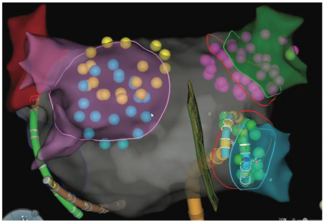

Optimal mapping of microreentrant atrial tachycardia (AT) circuits can be challenging, particularly in regions of scar. This case is illustrative of key considerations during mapping of microreentrant AT.